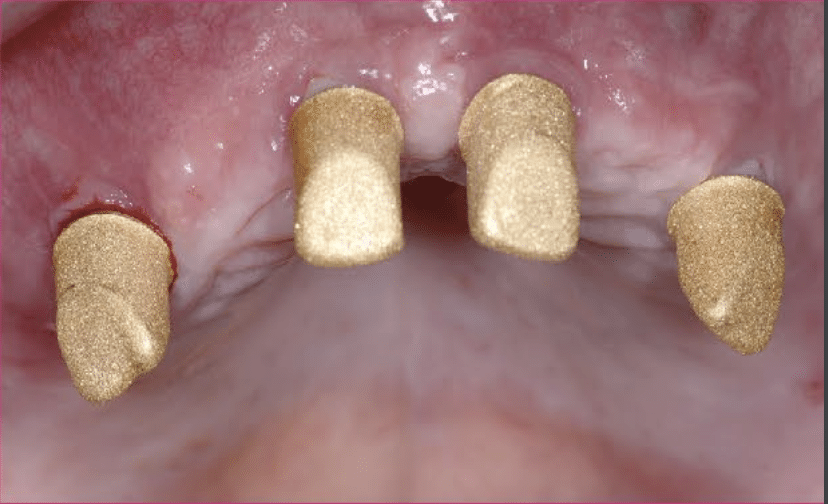

Nach entsprechender klinischer und röntgenologischer Diagnostik (Abb. 1a, b) wurden vier zweiteilige Keramikimplantate (Pure Ceramic, Straumann Group) für die Insertion im Oberkiefer Nach komplikationsloser dreimonatiger Osseointegration geplant (Abb. 2). Der Entscheidung bei der Auswahl dieser Medizinprodukte lag auch der Umstand zugrunde, dass die Implantate für systemimmanente Scanbodies kompatibel sind undüber sollte im digitalen Workflow hergestellt werden. Hierfür wurden zunächst die zum Implantatsystem passenden Scanbodies die sich schon bei der einteiligen Variante des Keramikimplantates (Monotype Pure Ceramic, Straumann Group) seitJahren auf dem Intraoralscanner (iTero, Align) digitalisiert (Abb. 5a).